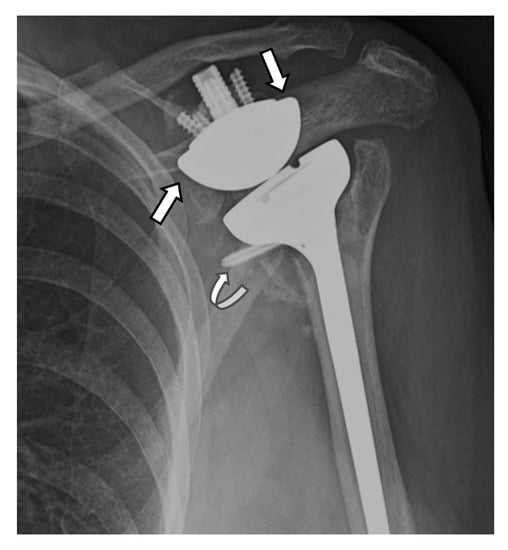

4.2.1. Loosening and Hardware Dissociation

5.2. Reverse Arthroplasty

Reverse Total Shoulder Arthroplasty (RTSA)

| Grade | Finding |

|---|---|

| 1 | Lucency extends to scapular pillar |

| 2 | Lucency contacts the inferior glenoid screw |

| 3 | Lucency extends over the inferior glenoid screw |

| 4 | Lucency extends under the metaglene/baseplate |